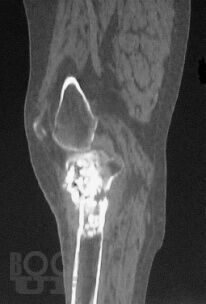

В настоящей монографии в сравнительном аспекте рассматриваются диагностические и дифференциально-диагностические возможности сцинтиграфии с неспецифическим туморотропным радиофармацевтическим препаратом и индикатором воспалительных процессов 199Tl-хлоридом. Авторами показана высокая эффективность сцинтиграфии с 199Tl-хлоридом в неспецифической индикации и дифференцильной диагностике опухолевых и воспалительных процессов опорно-двигательного аппарата, органов грудной клетки и прочих локализаций, приводятся диагностические и дифференциально-диагностические критерии этих процессов.